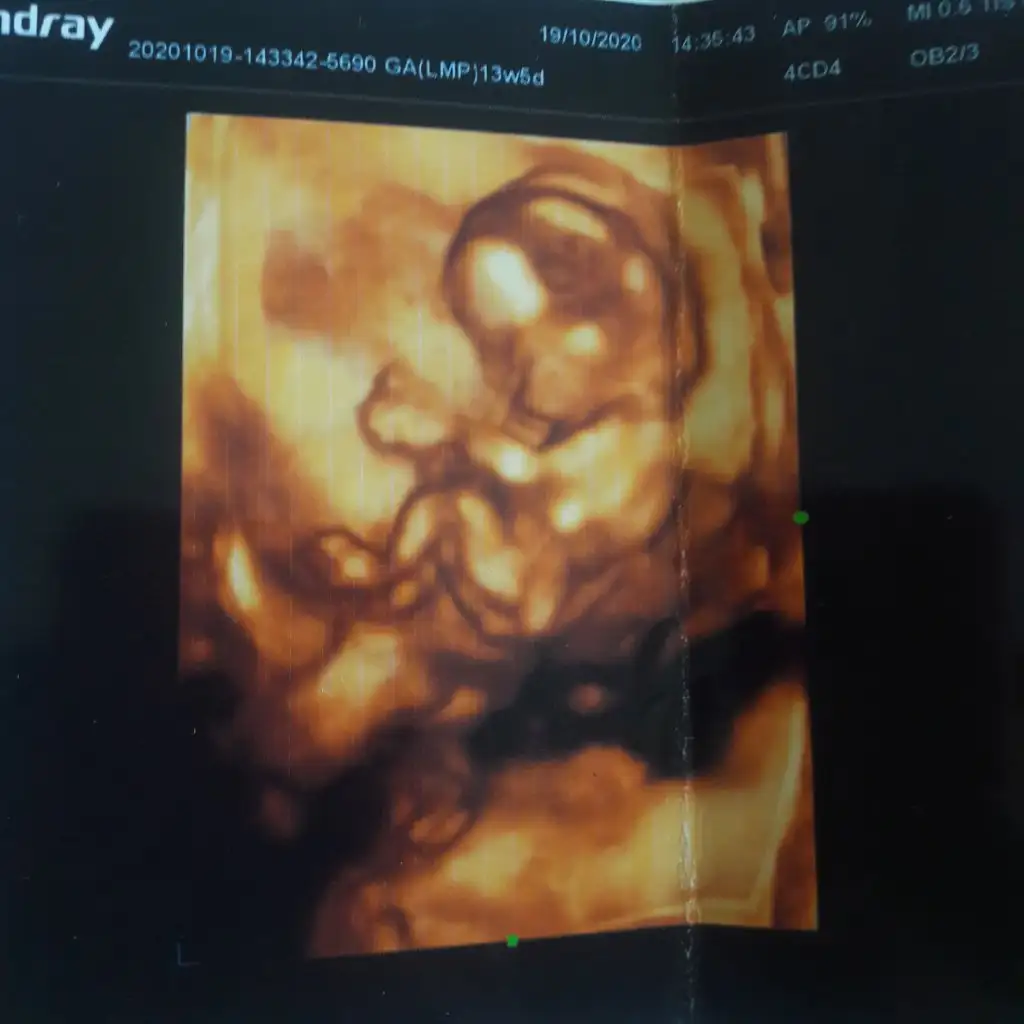

Renkli değil diğer USG varsa paylaşın burada nubu belli degil 11 12 13 haftalar olmalı13+5 günlük banada bakabilirmisiniz kızlarEki Görüntüle 2712490

Erkek gibi sanki yinede en iyi nub 11 12 13 haftalar olmalımerhabalar 14 haftalık hamileyım banada tahmınde bulunabılırmısınız

teşekkürler 30 kaımda kontolüm var ve oğluma bro mu sister mı gelecek artık öğreneceğiz :)Evet burada nub görünmüyor diğerinde karşıya bakıyor nubu karşıya bakan nubta erkek olma ihtimalini arttırırV varbihayalim